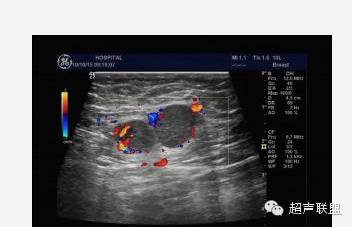

5.多普勒灵敏度和功率多普勒技术的改善,使观察乳腺内部的血管分布更为直接。在20世纪80年代初多普勒超声技术刚用于血管检测时,主要采用连续波多普勒,因为它有较高的灵敏度。乳腺肿块周围的血管内含有较高的血流速度被认为是恶性肿瘤的象征。现在,只需用彩色多普勒观察分布于肿块内外的血管数量即可作出同样的诊断。尽管对于多普勒信息的解释仍有异议,但多数研究者及ATL/FDA临床实验的结果确认了乳腺肿块中增加的血管分布预示了恶性肿瘤。

使用造影剂的缺点在于造价高,并需要静脉注射。而且,灵敏度更高的多普勒仪器的出现使得血流信号的增强已不像过去那么重要。图4显示,在移植入肝脏中的实验性肿块上运用造影剂后,组织的对比度增强。类似的增强是否也适用于乳腺组织亟待研究。

声像图表现:于右乳腺相当于六点钟,距约1.5cm处见一大小约1.0x0.6cm低回声肿物,边界尚清,形态不规,周边可检出动脉频谱样血流信号,RI为0.67,余腺体回声粗糙,未见占位性病变。右腋下另见数个淋巴结,较大的为1.4x0.8cm,边界清,周边呈低回声,中心部呈高回声。